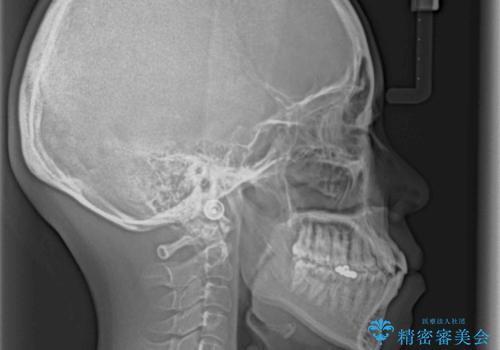

- 受け口傾向でクロスバイトの前歯を治したいとのことで来院された患者様です。

下顎骨が若干左側に変位していたため、右側にアンカースクリューを使用し、積極的に移動させながらインビザラインにて矯正治療を行うこととしました。

インビザラインによる矯正治療は、受け口傾向の治療に非常に適した方法であり、事前にシミュレーションに沿って治療を進めることできます。

今回の治療では骨格的な偏位があったためアンカースクリューを使用し、より確率の高い治療を行うことができました。